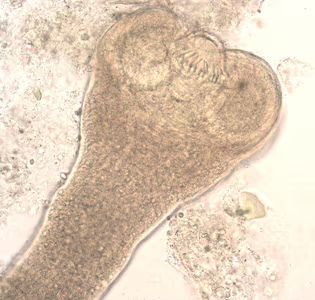

Intermediate hosts of Hymenolepis spp.

. When eggs are ingested by an arthropod intermediate host  (various species of beetles and fleas may serve as intermediate hosts), they develop into cysticercoids, which can infect humans or rodents upon ingestion

(various species of beetles and fleas may serve as intermediate hosts), they develop into cysticercoids, which can infect humans or rodents upon ingestion  and develop into adults in the small intestine. A morphologically identical variant, H. nana var. fraterna, infects rodents and uses arthropods as intermediate hosts. When eggs are ingested

, and oncospheres are released from the eggs and penetrate the intestinal wall of the host  , which develop into cysticercoid larvae. Species from the genus Tribolium are common intermediate hosts for H. diminuta. The cysticercoid larvae persist through the arthropod’s morphogenesis to adulthood. H. diminuta infection is acquired by the mammalian host after ingestion of an intermediate host carrying the cysticercoid larvae

, which develop into cysticercoid larvae. Species from the genus Tribolium are common intermediate hosts for H. diminuta. The cysticercoid larvae persist through the arthropod’s morphogenesis to adulthood. H. diminuta infection is acquired by the mammalian host after ingestion of an intermediate host carrying the cysticercoid larvae  . Humans can be accidentally infected through the ingestion of insects in precooked cereals, or other food items, and directly from the environment (e.g., oral exploration of the environment by children). After ingestion, the tissue of the infected arthropod is digested releasing the cysticercoid larvae in the stomach and small intestine. Eversion of the scoleces

. Humans can be accidentally infected through the ingestion of insects in precooked cereals, or other food items, and directly from the environment (e.g., oral exploration of the environment by children). After ingestion, the tissue of the infected arthropod is digested releasing the cysticercoid larvae in the stomach and small intestine. Eversion of the scoleces  occurs shortly after the cysticercoid larvae are released. Using the four suckers on the scolex, the parasite attaches to the small intestine wall. Maturation of the parasites occurs within 20 days and the adult worms can reach an average of 30 cm in length